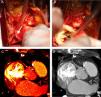

Painel A: dissecção cirúrgica do início da coronária direita revelando a sua origem na parede ântero-lateral esquerda da aorta e trajeto extramural e interarterial. Painel B: após transeção da aorta, constata-se origem coronária acima dos seios de Valsalva, posteriormente à comissura entre as cúspides direita e esquerda; notar a obliquidade do ostium coronário. Painéis C e D: tomografia computorizada multidetetores realizada após cirurgia de revascularização do miocárdio. As imagens de reconstrução multiplanar demonstram a anastomose látero-lateral (setas). As imagens de densidade elevada correspondem aos clips cirúrgicos empregues.

No presente caso, dada a origem alta e trajeto extramural da coronária direita (Figura 4, painel A), a sua reimplantação levaria a uma angulação exagerada do seu trajeto inicial ou ainda a uma implantação ainda mais alta e anormal, optando-se pela realização de uma anastomose látero-lateral à parede anterior da aorta, com bons resultados clínicos e no teste de isquemia.